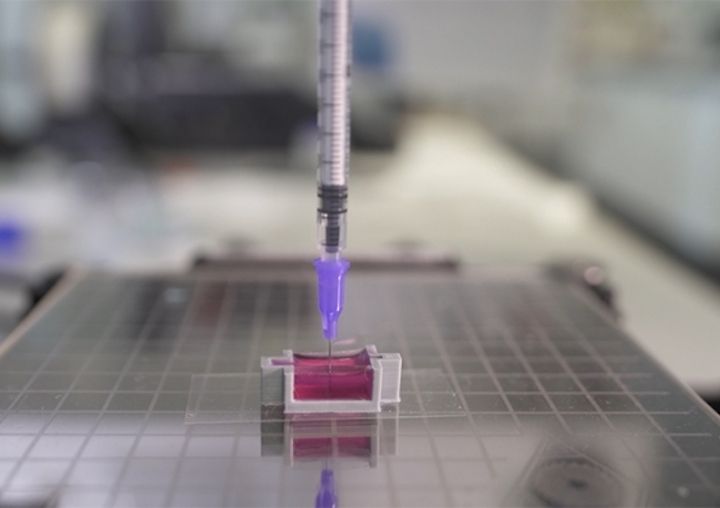

In-Body 3D Printing Under Development

There may soon be a way to 3D print bones directly into patients.

BioPrinting Breakthrough in Ireland

Researchers at Trinity College in Dublin have worked out a new process for 3D printing live, complex bone structures.